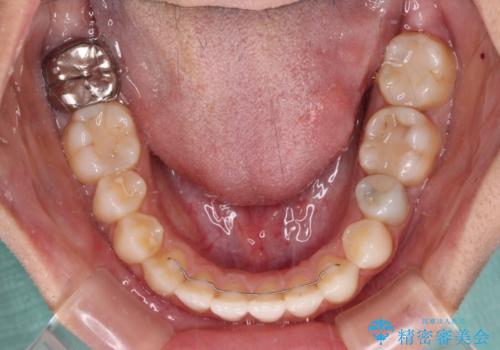

- オープンバイトのため、話しているときの見た目が気になるとのことで来院された患者様です。

下顎骨は左側にシフトしており、咬み合ったときには奥歯と前歯の一部しか接触していない状態でした。

骨格的な左右差は歯列矯正は改善できないため、上下歯列が全体的に接触することをゴールとしてインビザラインにて矯正治療を行うこととしました。

前歯のデコボコの解消と並行して上下の奥歯を圧下させるようにすることで、前歯を接触させるように計画しました。

上下の隙間に舌が入り込むことがオープンバイトの原因であったため、舌の筋肉のトレーニングも並行して行い、後戻りの抑制を図りました。